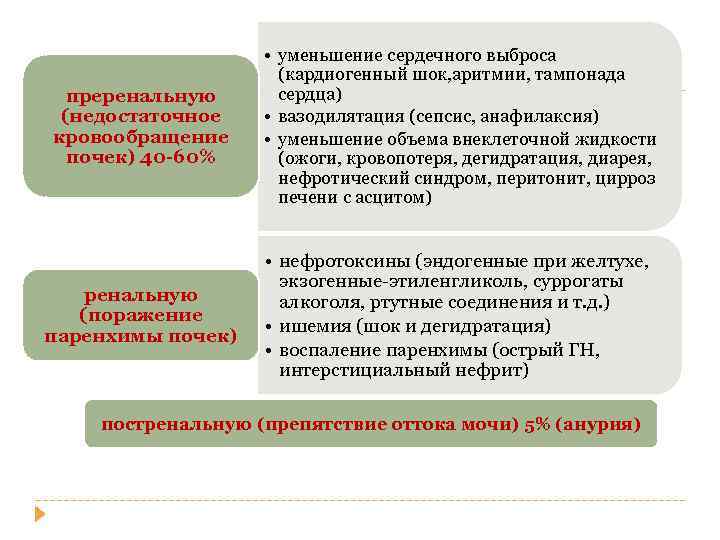

преренальную (недостаточное кровообращение почек) 40 -60% • уменьшение сердечного выброса (кардиогенный шок, аритмии, тампонада сердца) • вазодилятация (сепсис, анафилаксия) • уменьшение объема внеклеточной жидкости (ожоги, кровопотеря, дегидратация, диарея, нефротический синдром, перитонит, цирроз печени с асцитом) ренальную (поражение паренхимы почек) • нефротоксины (эндогенные при желтухе, экзогенные-этиленгликоль, суррогаты алкоголя, ртутные соединения и т. д. ) • ишемия (шок и дегидратация) • воспаление паренхимы (острый ГН, интерстициальный нефрит) постренальную (препятствие оттока мочи) 5% (анурия)